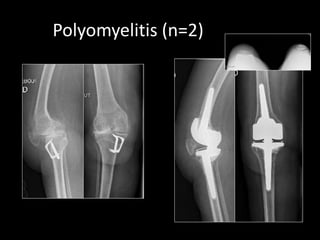

Polyomyelitis (n=2)

– Polyomyelitis …